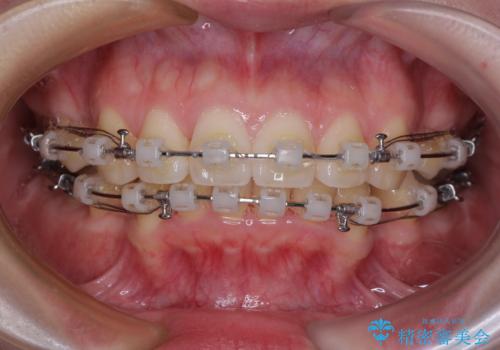

- 矯正装置

- クリアブラケット

順調に治療が進み、2年弱で想定していたとおりの仕上がりにて治療を終えることができました。